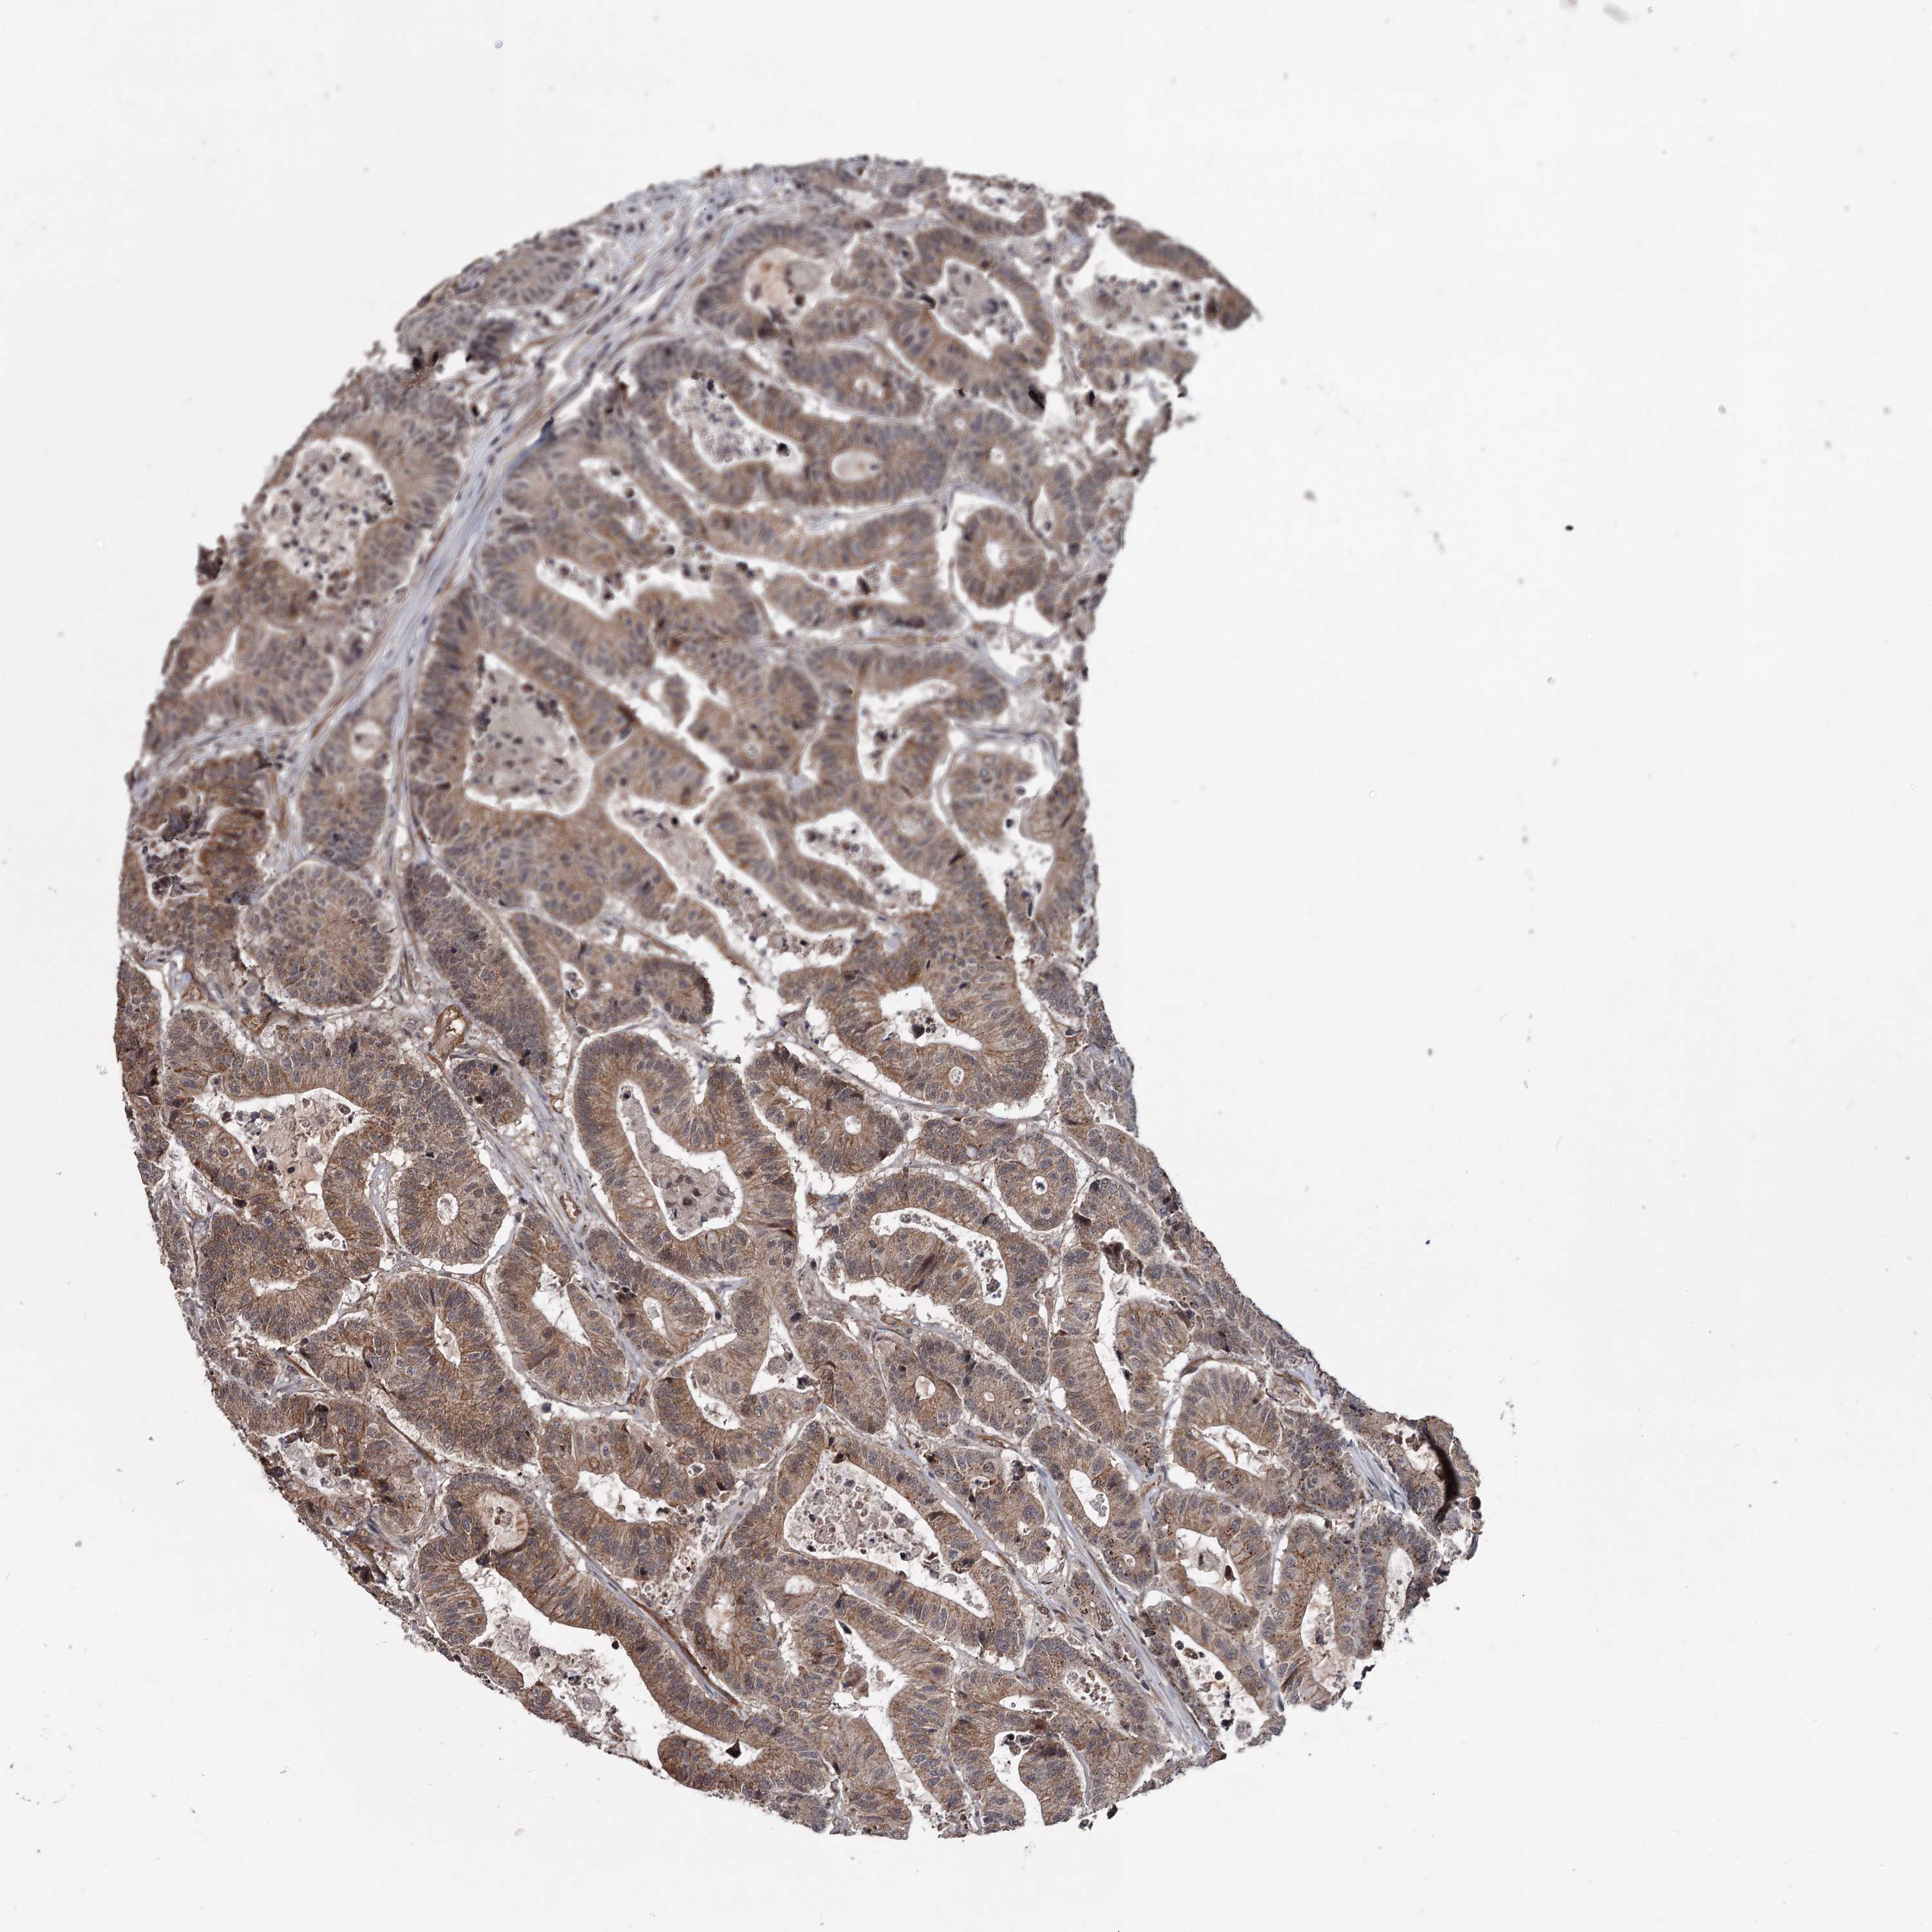

Colorectal cancer

Colon adenocarcinoma